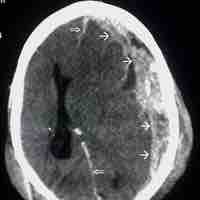

Thumbnail

Cerebrovascular Accident

A cerebrovascular accident results from loss of oxygenated blood to a region of the brain and is typically accompanied by neuronal loss.

Transient Ischemic Attacks

A transient ischemic attack is similar to a stroke; though without permanent damage, it can serve as an important risk factor for stroke.